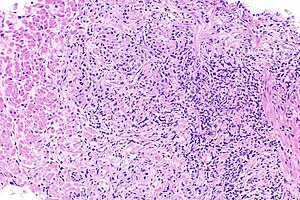

Файл:Acute inflammatory exudate.jpg

Острый воспалительный экссудат